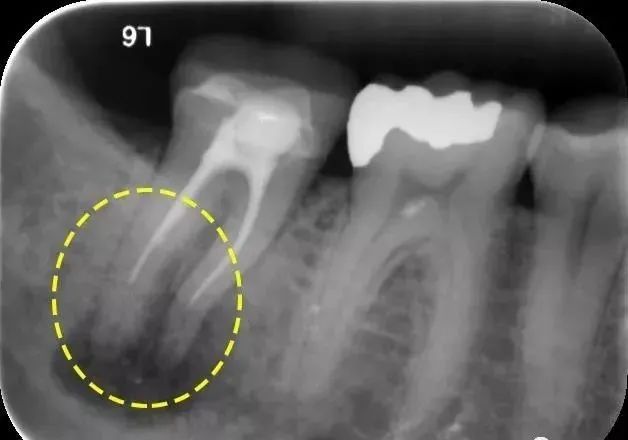

由于工作长度测量不准导致根管封闭剂超充(A)或者封闭剂和牙胶超充(B)